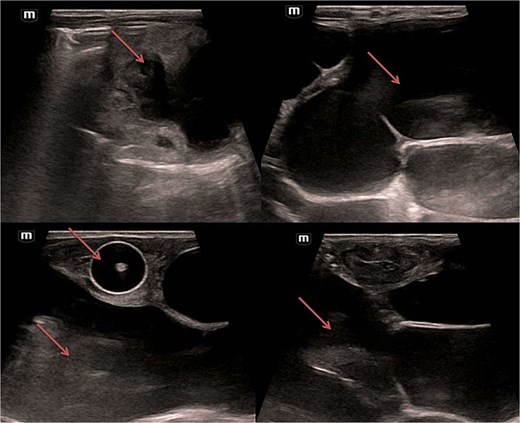

Abdominal and scrotal ultrasonography demonstrated multilocular cystic hydronephrosis with thinning of renal parenchyma, extending into the pelvis, and absence of testes within the scrotum. Both testes were located intra-abdominally between bowel loops (left 7 × 4.5 mm, right 6 × 5.5 mm) (Figs 2 and 3). Abdominal X-ray after percutaneous nephrostomy with contrast revealed pooling in both kidneys without ureteric passage, suggesting bilateral ureteropelvic junction obstruction (UPJO) (Fig. 4).